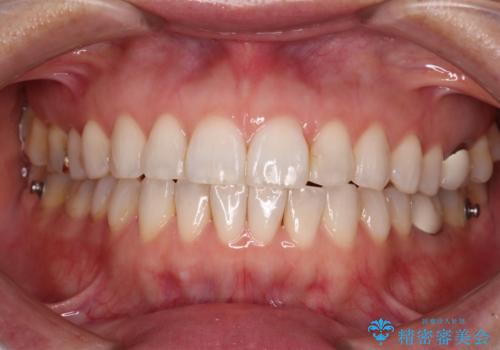

ちょっとしたデコボコをしっかりと改善したい インビザライン矯正

- 前歯のデコボコと上下スペースと前歯の隙間を気にして来院された患者様です。

目立たない装置を希望とのことでインビザラインにより、デコボコを解消しつつ、上下の前歯の隙間を閉じていくこととしました。

デコボコはあっという間に解消されましたが、上下前歯の隙間がなかなか解消されませんでした。

飲み込みの際に舌を前方に突出する癖があり、飲み込みの度に前歯に強く接触していたため、上下前歯の隙間が維持されていました。

舌の訓練を徹底していただいたことで、徐々に隙間は解消され、きれいな歯列に整えることができました。